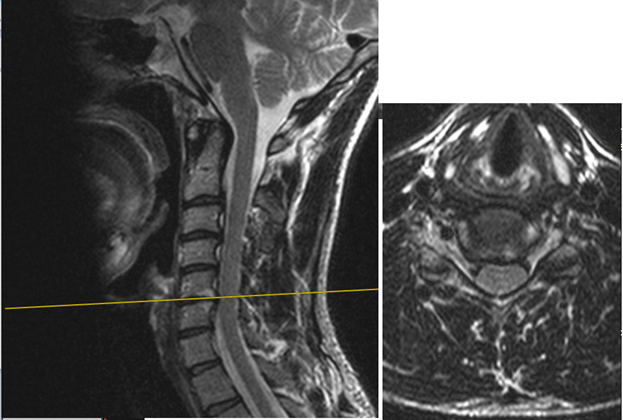

Вот мой снимок:

image

Два снимка – первый саггитальный срез и соответствующий ему аксиальный срез (второй снимок). В общем-то видно, что есть относительный центральный стеноз + небольшое сдавление спин. мозга.